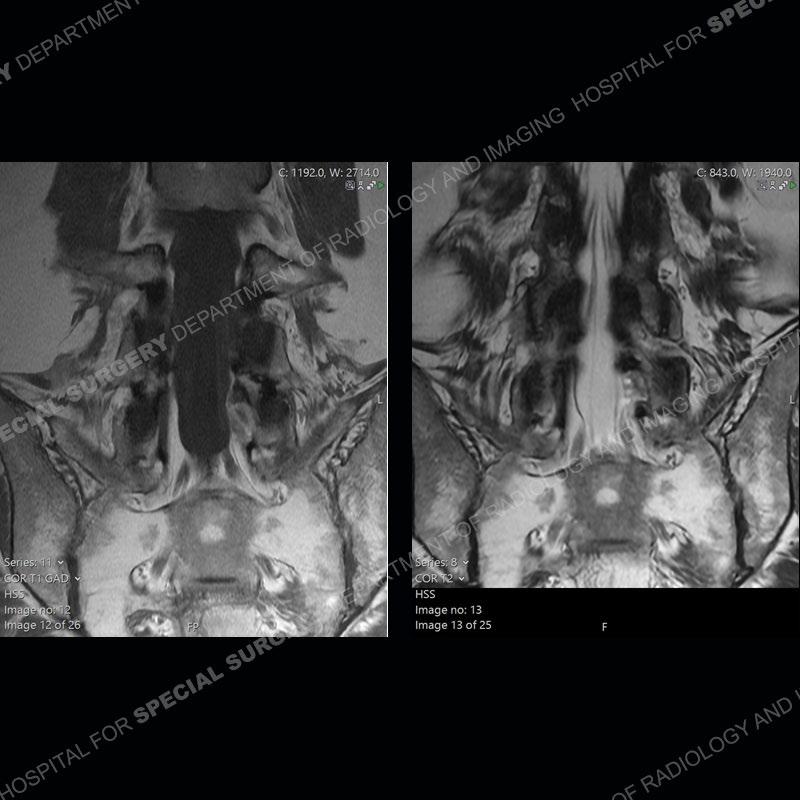

Post operative changes are seen on the left side at L5-S1 where there is near complete removal of the left sided L5 lamina, partial resection of the left L5-S1 facet joint, and resection of the left sided ligamentum flavum. In the anterolateral epidural space about the subarticular recess is a mass that demonstrates similar T1 and T2 signal characteristics to the adjacent degenerated disc. There is enhancement about the periphery of the mass, but the majority of this somewhat geographic or polyploid mass demonstrates no enhancement. The mass exerts prominent mass effect on the left S1 axillary sleeve/proximal nerve root. The left S1 nerve root shows enlargement and increased enhancement as compared to the contralateral right side.

Diagnosis: Recurrent Disc Herniation

Not as much of a diagnostic dilemma as some other cases but more so just a very nice example of what can be a difficult assessment at times. The evaluation of granulation tissue/scar/epidural fibrosis vs. disc herniation particularly in the earlier post operative period can be very difficult. Clues that can assist in identifying a disc herniation are a more geographic or polypoid nature to the mass, signal characteristics similar to the adjacent degenerated disc, mass effect upon the thecal sac/adjacent neural structures, and a typical enhancement pattern. As the disc material is avascular, as long as imaging is performed in a relatively rapid fashion after contrast administration (within 20-30 minutes), the granulation tissue around the disc will enhance but the disc material itself will not. If there is a marked delay between contrast administration and imaging, there may be diffusion of contrast into the disc making the assessment very difficult. The marked utility of contrast to help delineate disc vs. scar has led to our institution employing contrast fairly uniformly within the first two years following surgery.